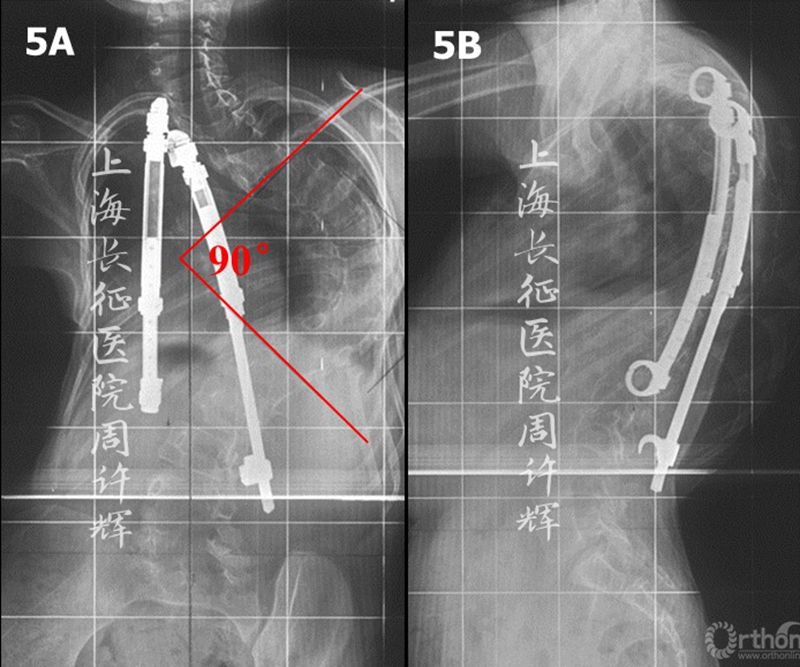

女性,3岁时发现背部畸形(图1),X片示侧弯60°。外院行支具治疗5年(8岁)后,复查全脊柱X片示支具内侧弯65°(图2)。继续外院行VEPTR(第4-9肋、第2肋-第2腰椎)治疗,术后侧弯69°(图3)。术后2年(10岁)复查发现侧弯80°、VEPTR第9肋骨折、第2肋脱钩(图4)。进行内固定更换,VEPTR(第4-10肋、第4肋-第2腰椎),术后3年(13岁)复查示侧弯90°(图5)。